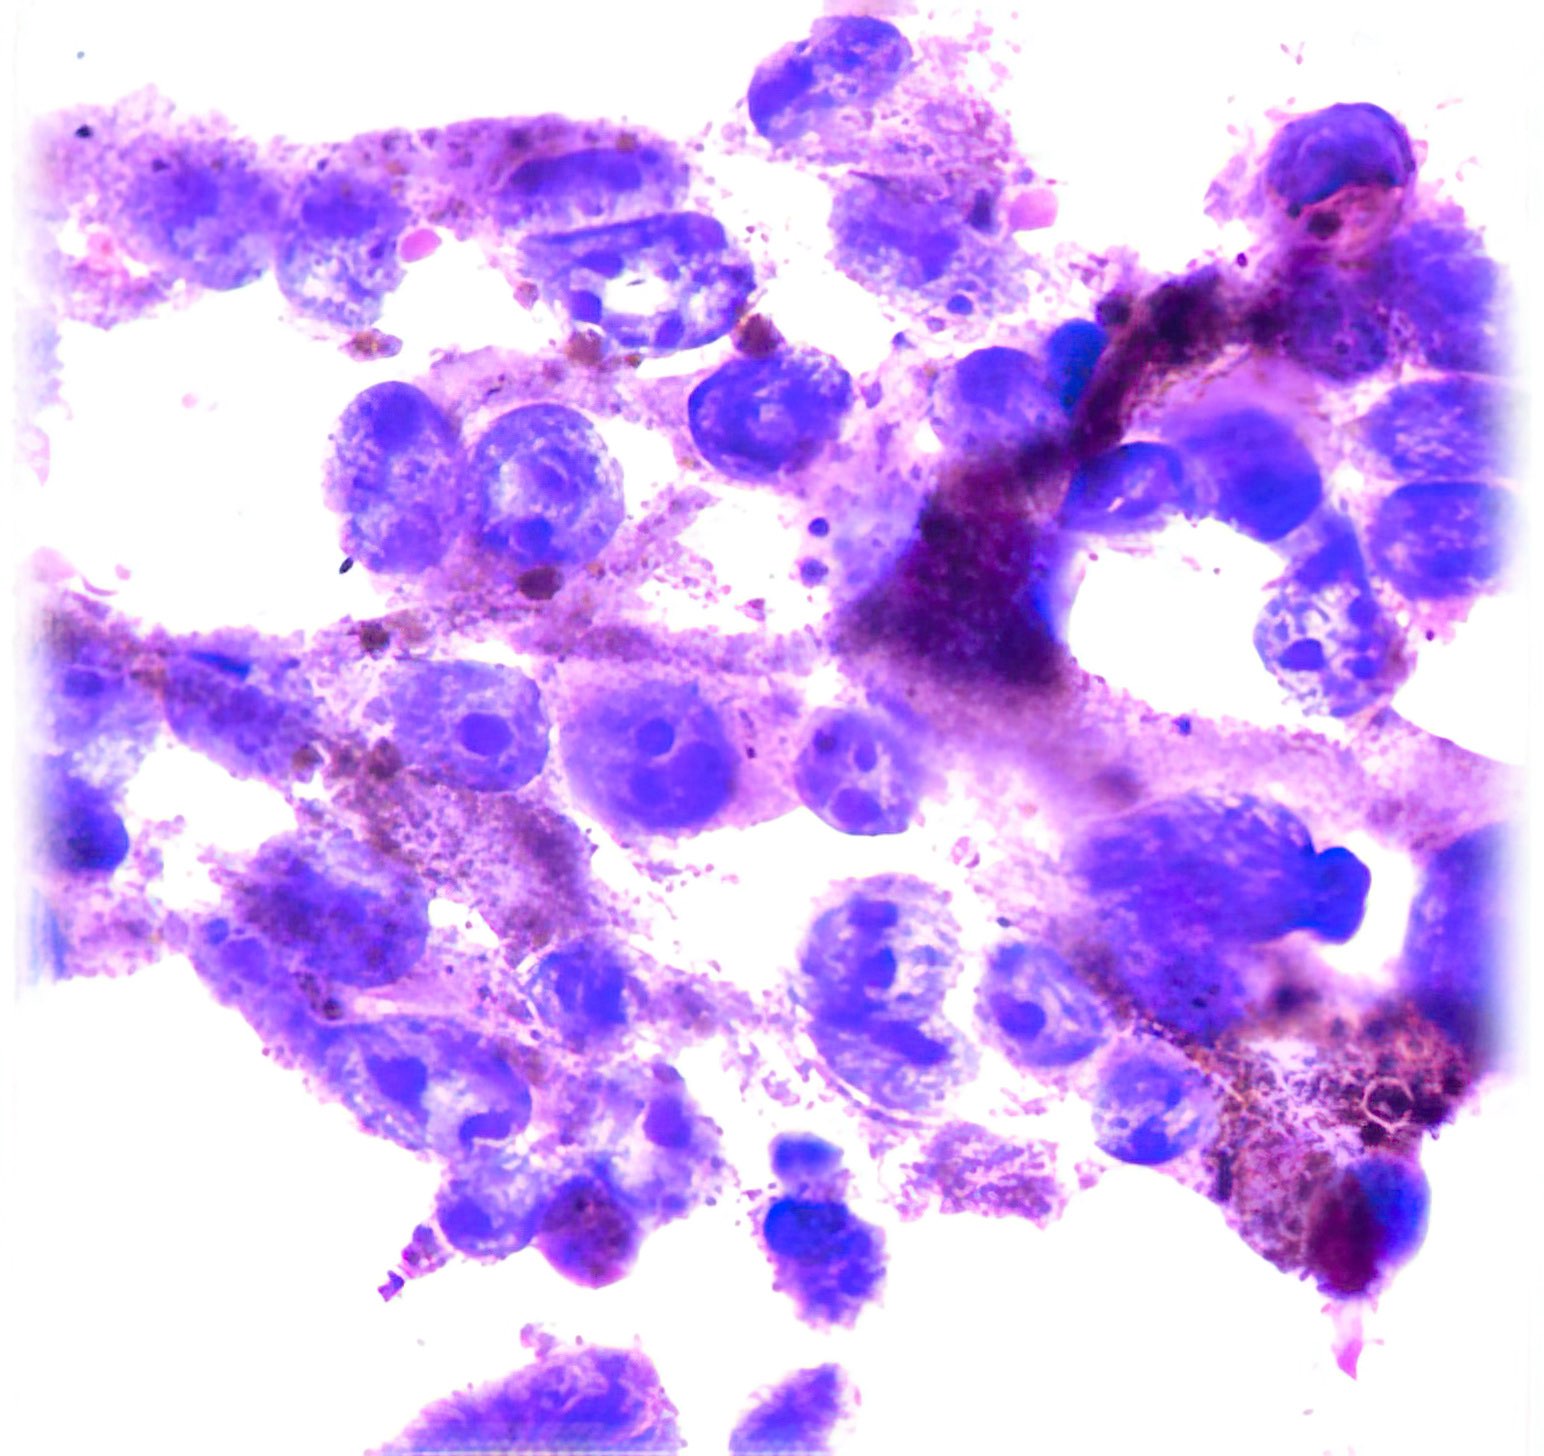

Abbildung 1 – 4: HE-Färbung; 1 – 4, original Obj. 40x, Abb. 4:

zusätzlich vergrößert

Invasive breast carcinoma (IBC NST G3)

Die sich teils überlagernden Zellen erscheinen meist nacktkernig oder haben nur wenig Zytoplasma. Die Kerne variieren deutlich in Form und Größe, sind grob strukturiert und zeigen vereinzelt kleine Chromozentren und Protrusionen. Im Hintergrund etwas Zelldetritus.

Die histologischen Bilder (Abb. 1 und 2) bestätigen die zytologische Diagnose. Weite Teile des Gewebes sind durchsetzt von Tumorzellen, die nur angedeutet Verbände bilden und deutlich polymorphe Kerne aufweisen.